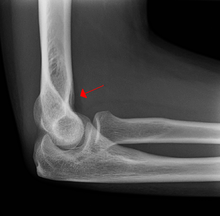

Fat pad sign

On an elbow X-ray, the fat pad sign, also known as the sail sign, suggests an occult fracture. Its name derives from the fact that it has the shape of a spinnaker (sail).[1] It is caused by displacement of the fat pad around the elbow joint. Both anterior and posterior fat pad signs exist, and both can be found on the same X-ray.

In children, a posterior fat pad sign suggests a condylar fracture of the humerus. In adults it suggests a radial head fracture. The fat pad sign only occurs after an intra-articular fracture.

The fat pad sign is invaluable in assessing for the presence of an intra-articular fracture of the elbow. An anterior fat pad is often normal. However a posterior fat pad seen on a lateral x-ray of the elbow is always abnormal. The patient will be unable to flex their elbow and requires orthopaedic input.[2]

The posterior fat pad is normally pressed in the olecranon fossa by the triceps tendon, and hence invisible on lateral radiograph of the elbow.[3] When there is a fracture of the distal humerus, or other pathology involving the elbow joint, inflammation develops around the synovial membrane forcing the fat pad out of its normal physiologic resting place. This is visible as the "posterior fat pad sign" and is often the only visible marker of a fracture, particularly in the pediatrics population.